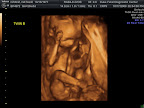

Today was a wonderful day at the doctor. We got to check on the growth of both babies and they are doing quite well. Baby Girl Kranz is now 2.6 lbs and Baby Boy Kranz is 2.5 lbs. We are thrilled about this growth and it explains the rapid growth everyone has affectionately noted in my belly pics. There is little room for movement and there is even less room to get good pictures. We are really down to pictures of parts and even at that, they are quite squished. Both babies are pointed down but it became quite apparent why I feel like one of them is kicking me in the rib cage all the time when we found the boy's femur right up against my ribs. The girl is still a girl and the boy is WOW still a boy! Daddy is a proud man!!!